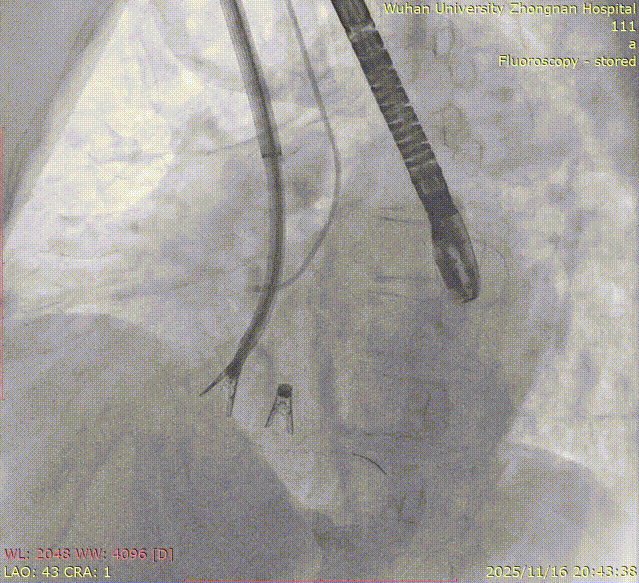

The entire procedure was guided by both Transesophageal Echocardiography (TEE) and Digital Subtraction Angiography (DSA).

Left Atrial Appendage Closure (LAAC):The delivery system was successfully advanced into the left atrium. Precise measurements of the LAA orifice and depth were taken under multi-angle TEE and DSA guidance. Given the LAA's large orifice (nearly 34mm), conical cauliflower shape, and shallow usable depth, a LACBES2434 occluder was selected. Using the "extreme coin technique," the closure was successfully achieved.

DSA

K-Clip® Tricuspid Annuloplasty (Seamless Transition):Immediately after LAAC, the operators established a new vascular access route and advanced the K-Clip® delivery system directly into the right atrium, targeting the posterior-septal and anterior-posterior commissures of the tricuspid annulus. Under real-time ultrasound guidance, the team precisely anchored, clipped, and released the devices.

5.Right coronary angiography confirming no impact on the RCA after clipping.

8.Right coronary angiography confirming no impact on the RCA before releasing the second implant.